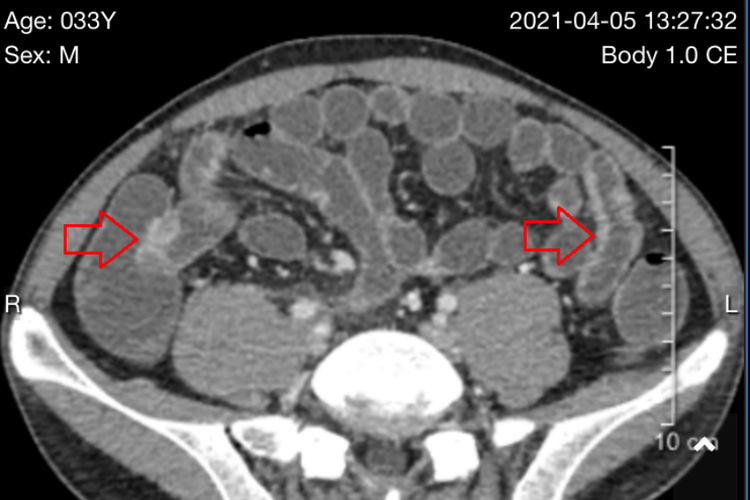

下腹部CT可检查结肠、阑尾、膀胱、男性睾丸及女性子宫、卵巢等部位。

下腹部CT常用于诊断肠梗阻、阑尾炎、膀胱肿瘤、前列腺增生、子宫良恶性肿瘤等疾病。

下腹部CT分为肠道CT检查、泌尿系统CT检查、盆部CT检查,检查部位包括结肠、阑尾、膀胱、睾丸、子宫等。

泌尿系统CT检查

全尿路CT检查范围从第12胸椎上缘至耻骨联合下缘;肾脏CT检查,扫描范围包括第12胸椎上缘至第3腰椎下缘;膀胱CT检查,扫描范围上至髂前上棘连线,下达耻骨联合下缘。

适用范围包括泌尿系统先天性异常、泌尿系结石与钙化、尿路梗阻、肾脏囊肿性病变、肾脏输尿管与膀胱肿瘤、泌尿系感染性病变以及外伤等。